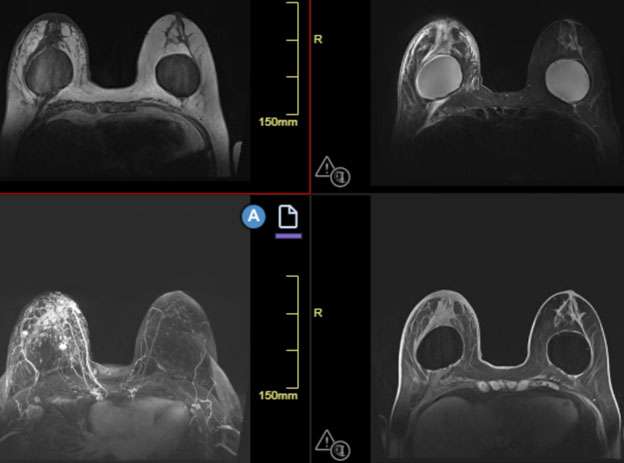

When MRI is performed, findings may include a heterogeneously enhancing mass and skin thickening. MRI is the most accurate imaging technique in detecting primary breast parenchymal lesions in cases of inflammatory breast cancer and may assist in delineation of disease extent (Figure 2).